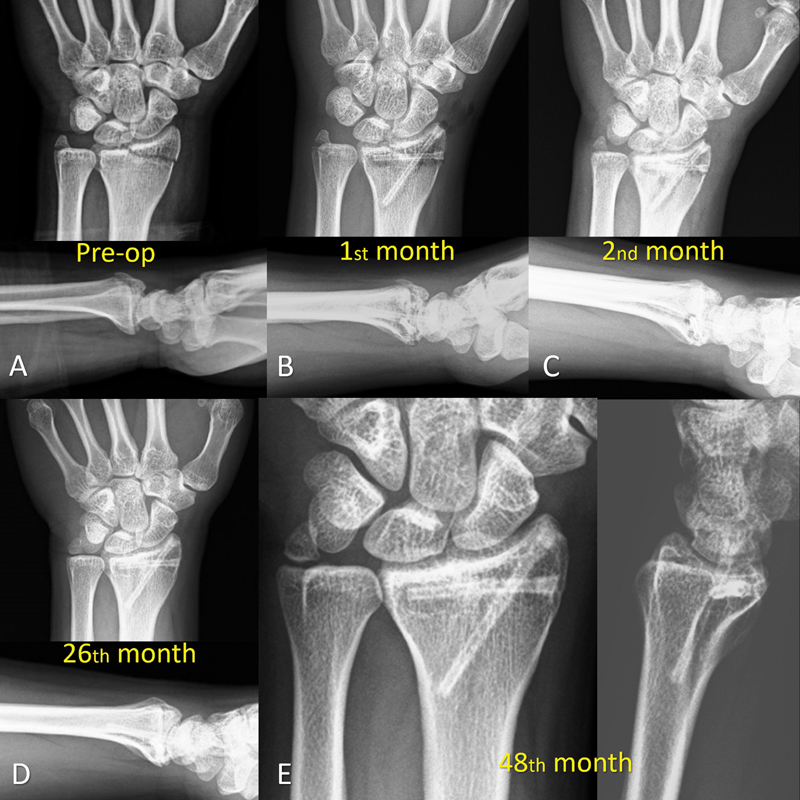

Fig. 1.

( A ) Anteroposterior and lateral wrist radiographs at initial admission showing the radial styloid fracture. ( B ) Fixation was achieved with two crossed magnesium screw. Radiographs at 2nd month ( C ) and 26th month ( D ) showed the union of the fracture with the gradual disappearance of gas around the screws. ( E ) Final follow-up at the 48th month.